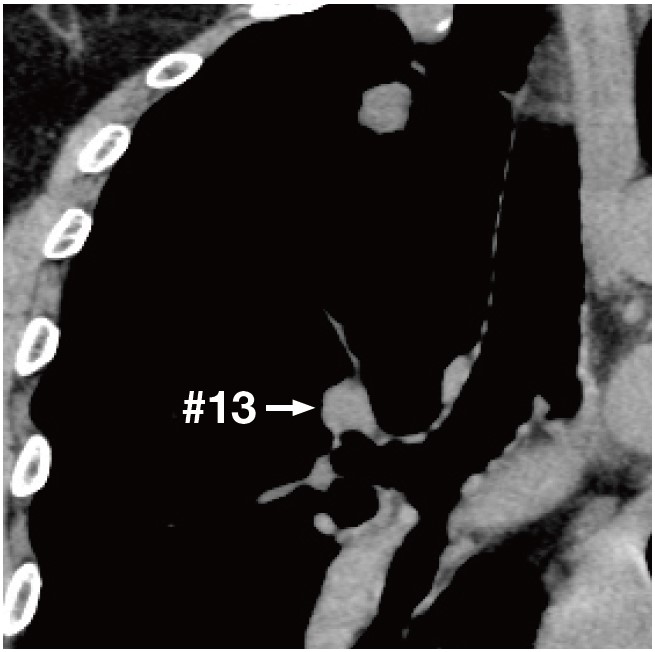

As for ViziShot 2 25G needle, the flexibility further surpasses ViziShot 2 FLEX and along with its superior puncture capability, it is best suited for the most difficult cases requiring puncturing under extreme angulation (Image 3).

Along with the thin diameter, the risk for hemorrhage is lower than with other gauges, making the 25G one of our main options when performing cases with lesions located in the vicinity of main blood vessels and cases which require puncturing through blood vessels (Image 3).